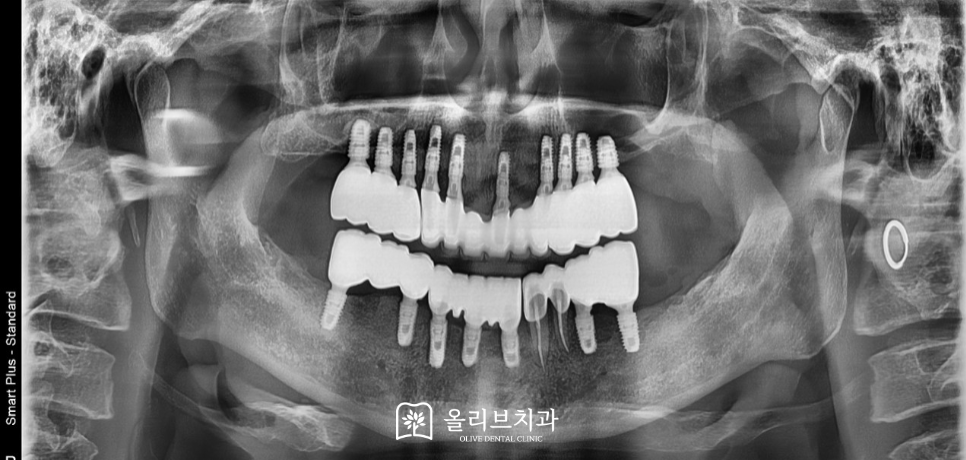

이후 상악에는 총 10개, 하악에는 총 7개의 임플란트를 식립하였고 식립된 임플란트에 맞게 임시치아를 제작하여 재적응을 도우며 최종적으로는 안정된 보철물을 이용해 교합과 저작 기능을 모두 회복하였습니다.

환자분께서는 꽤 긴 치료 기간 동안 성실히 내원해 주셨고 그 덕분에 무리 없이 기능 회복을 이룰 수 있었습니다. 최종 치료 후에는 “진작에 치과에 왔으면 좋았을 걸”이라며 만족스러운 웃음을 지으셨고, 치료에 대한 고마움을 여러 번 표현해주셨습니다.